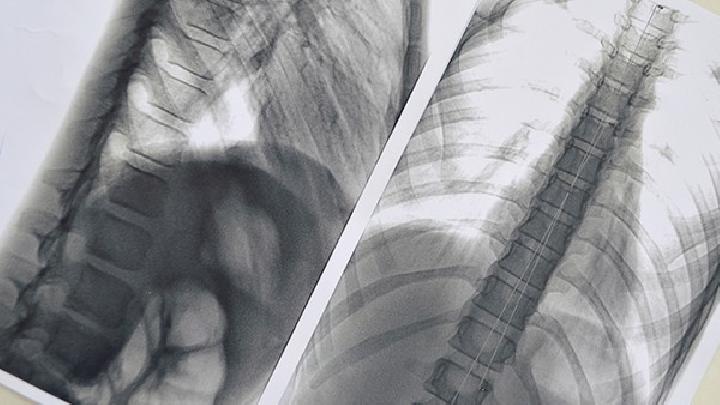

1.胸部放射线检查

常用于提示肺动脉高压的X线征象:

1、右下肺动脉横径增宽,国人正常值小于15mm;

2、肺门宽度与1/2胸廓横径比增加;

3、肺门胸廓指数增加,回肺动脉段突出,正常值小于3mm;

4、肺门动脉扩张与外围纹理纤细形成鲜明的对比或呈“残根状”;

5、心胸比率增加,正常小于0.50。需指出,轻、中度原发性肺动脉高压的胸部X线可无异常所见,重症患者改变明显,诊断的敏感性较高。